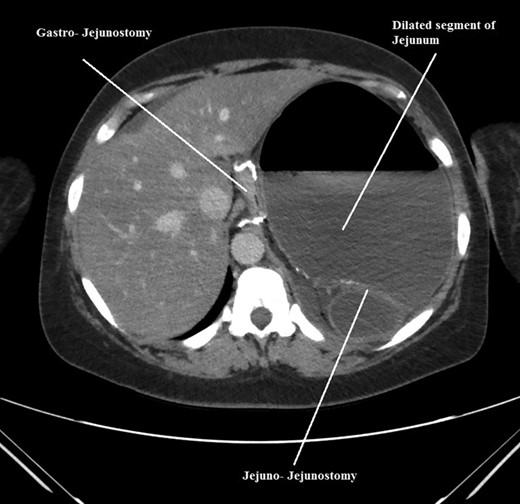

The intraoperative findings were not consistent with the radiological findings (Figs 1–4). As shown in the CT scan of abdomen and pelvis; multiple loops of dilated small bowel were seen, more predominantly dilated and matted bowel complex just above the spleen. The dilated bowel complex was decompressed using needle aspiration to help reduction of the bowel loops. The ileo cecal junction was then identified and traced back to the perisplenic hilar region. The trifurcation of three bowel loops (Roux limb, biliopancreatic limb and common limb) were identified with identification of ligament of Treitz. The prior gastric bypass was of ante colic- ante gastric type and Peterson’s defect was not closed. The above described bowel trifurcation had sunken postero- inferior to the spleen and had herniated through a potential space underneath the spleen and torsed around the splenic vessels and hilum. This picture was consistent with perisplenic small bowel volvulus. As noted earlier there was a massively dilated proximal small bowel segment above the spleen, displacing it caudally. Careful adhesiolysis was performed inferior to the spleen to release the segment of the trifurcation. The bowel segments once reduced were assessed and appeared viable. Of note, the spleen appeared better perfused after reduction. The remnant hernia defect of size 2 × 3 × 2.5 cm around the hilar region was then approximated using interrupted non-absorbable sutures. Enterotomy at the decompression site was closed with non absorbable suture. All potential sites of IH were re-examined and there was no evidence of any other internal herniation. Coelomic cavity was thoroughly irrigated and operation concluded successfully. Postoperative hospital stay was uneventful, and the patient was discharged home after two days.

Coronal CT scan of abdomen and pelvis showing volvulized bilio- pancreatic and Roux limbs within the obstructed segments in the splenic hilar region.